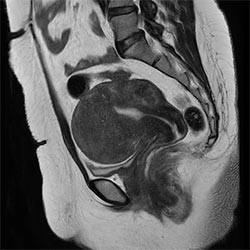

Pelvis